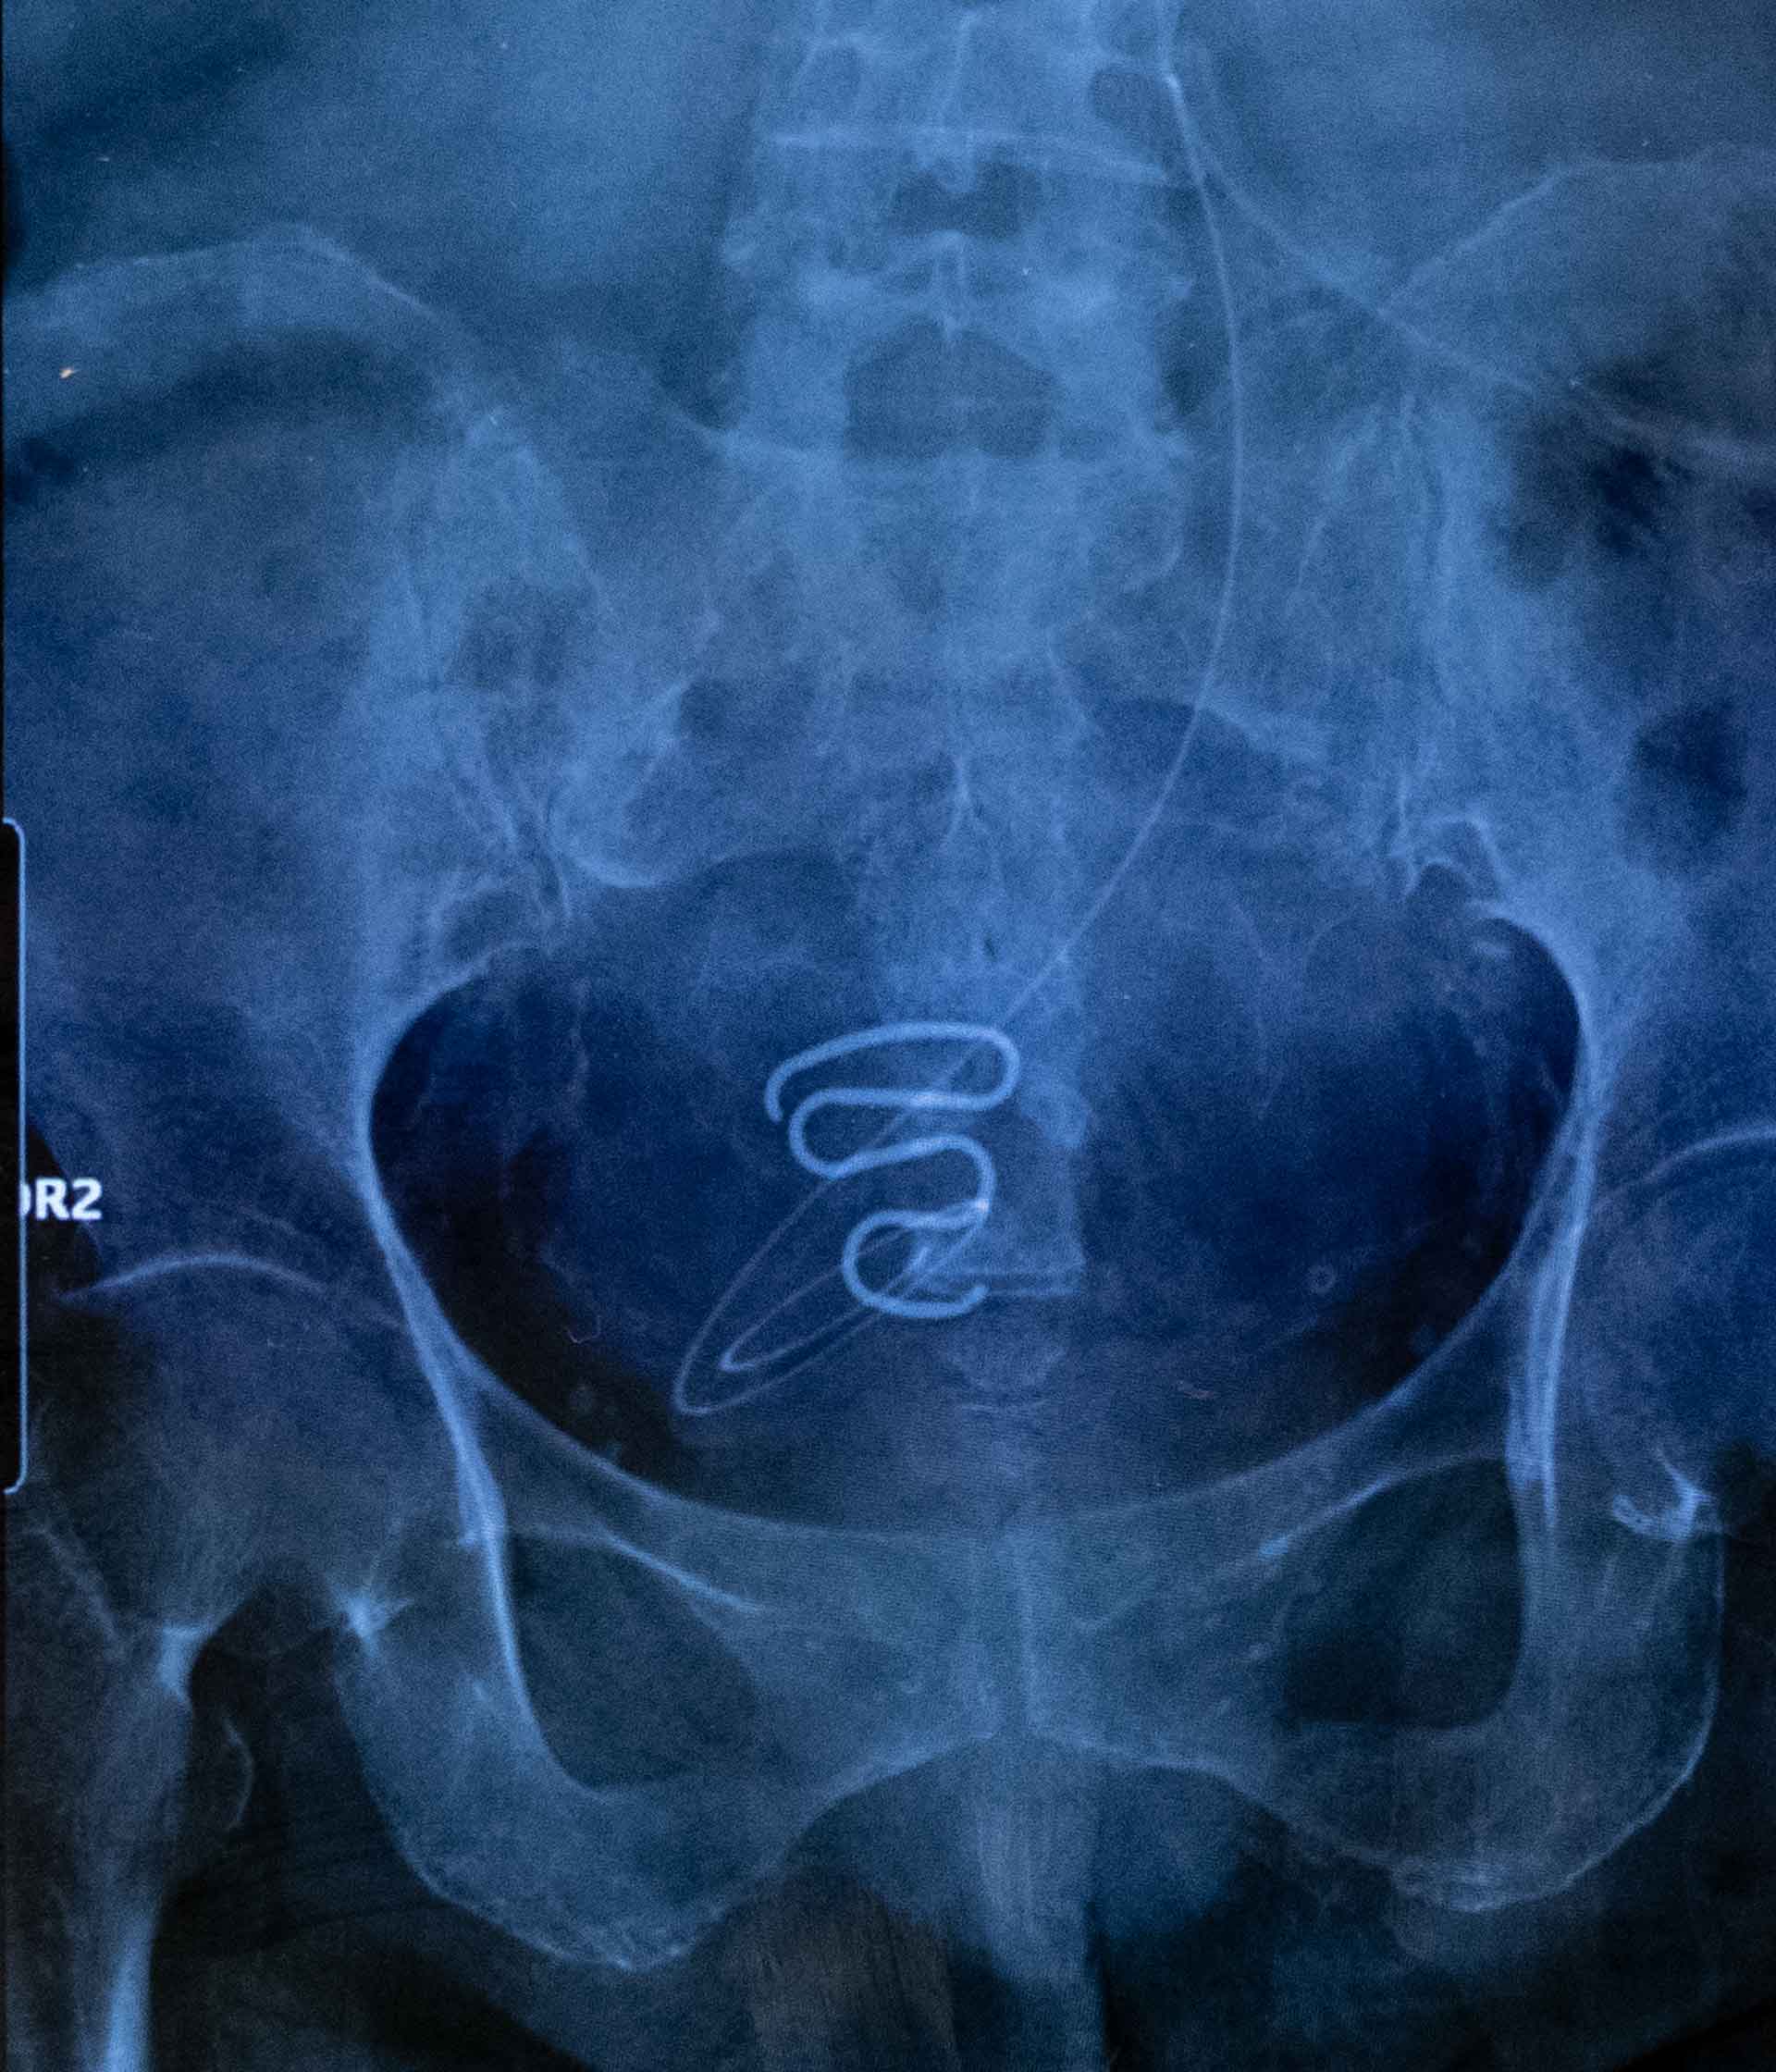

Sur la radio d’une patiente récupérée par Aviaja Siegstad, gynécologue à l’hôpital de Nuuk, apparaît le type de stérilet utilisé pendant la Spiralkampagnen. Inadapté au corps des adolescentes, il était souvent à l’origine de douleurs, de saignements, voire d’infections graves. Crédit photo : Juliette Pavy.